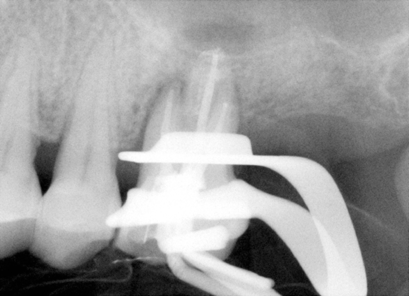

| 图七 牙周手术中:结石(箭头) | 图八 根尖切除前根尖片 |

2010-1-22 病人回诊所仍觉得疼痛没有改善,冷热痛,夜间痛,要求拔牙,检查表明:左上6号牙有轻度扣痛,颊侧根分叉处,以及鄂侧根鄂面有探痛,分析术前X光片(图八),好像远中根牙胶尖充填不到位,可能是术后疼痛原因,残余牙髓炎,所以我们准备作根尖切除术。翻瓣,根尖骨板完整,用高速牙钻开窗,一时找不到远中根尖,再拍一张根尖片(图九),适当调整后,我们找到了远中根尖,并作了切除术(图十),然后根尖倒充(IRM,图十一),生理盐水冲洗,缝合伤口。